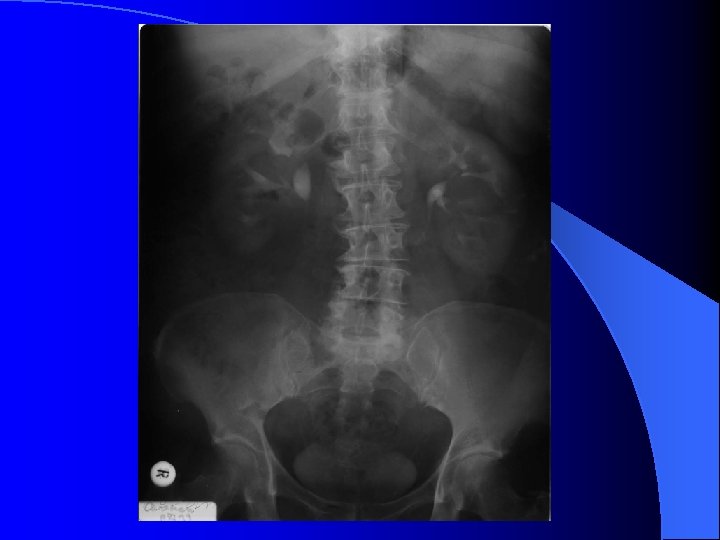

RRVS tehnic - ultimele doua coaste ( sup. ) - simfiza pubiana (inf. ) l calcificări - aparat urinar ( parenchim renal, calculi, prostatice ) - extraurinare ( arteriale, vezica biliara, pancreatice, ganglionare, fleboliti. . ) l umbre renale - pozitie, dimensiuni, contururi, intensitate l umbra m. psoas l

RRVS Nefrograma normală